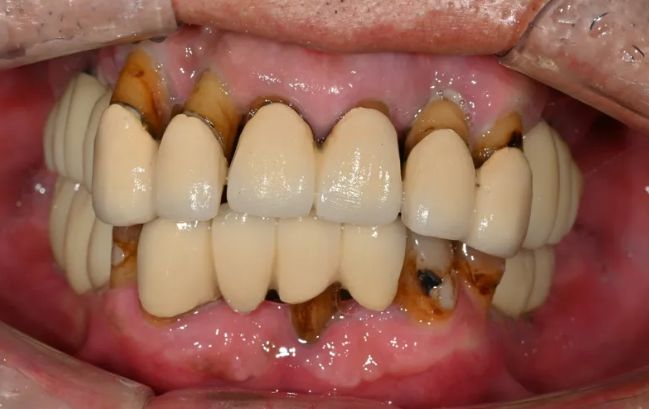

-

2021-09-06

2022-03-0560대 남성, 수면 전체 임플란트 13개 식립